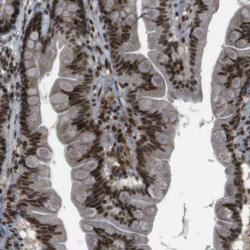

Supportive validation

- Experimental details

- Immunohistochemical staining of human small intestine shows strong nuclear positivity in glandular cells.

- Validation comment

- Staining pattern consistent with experimental and/or bioinformatic data.